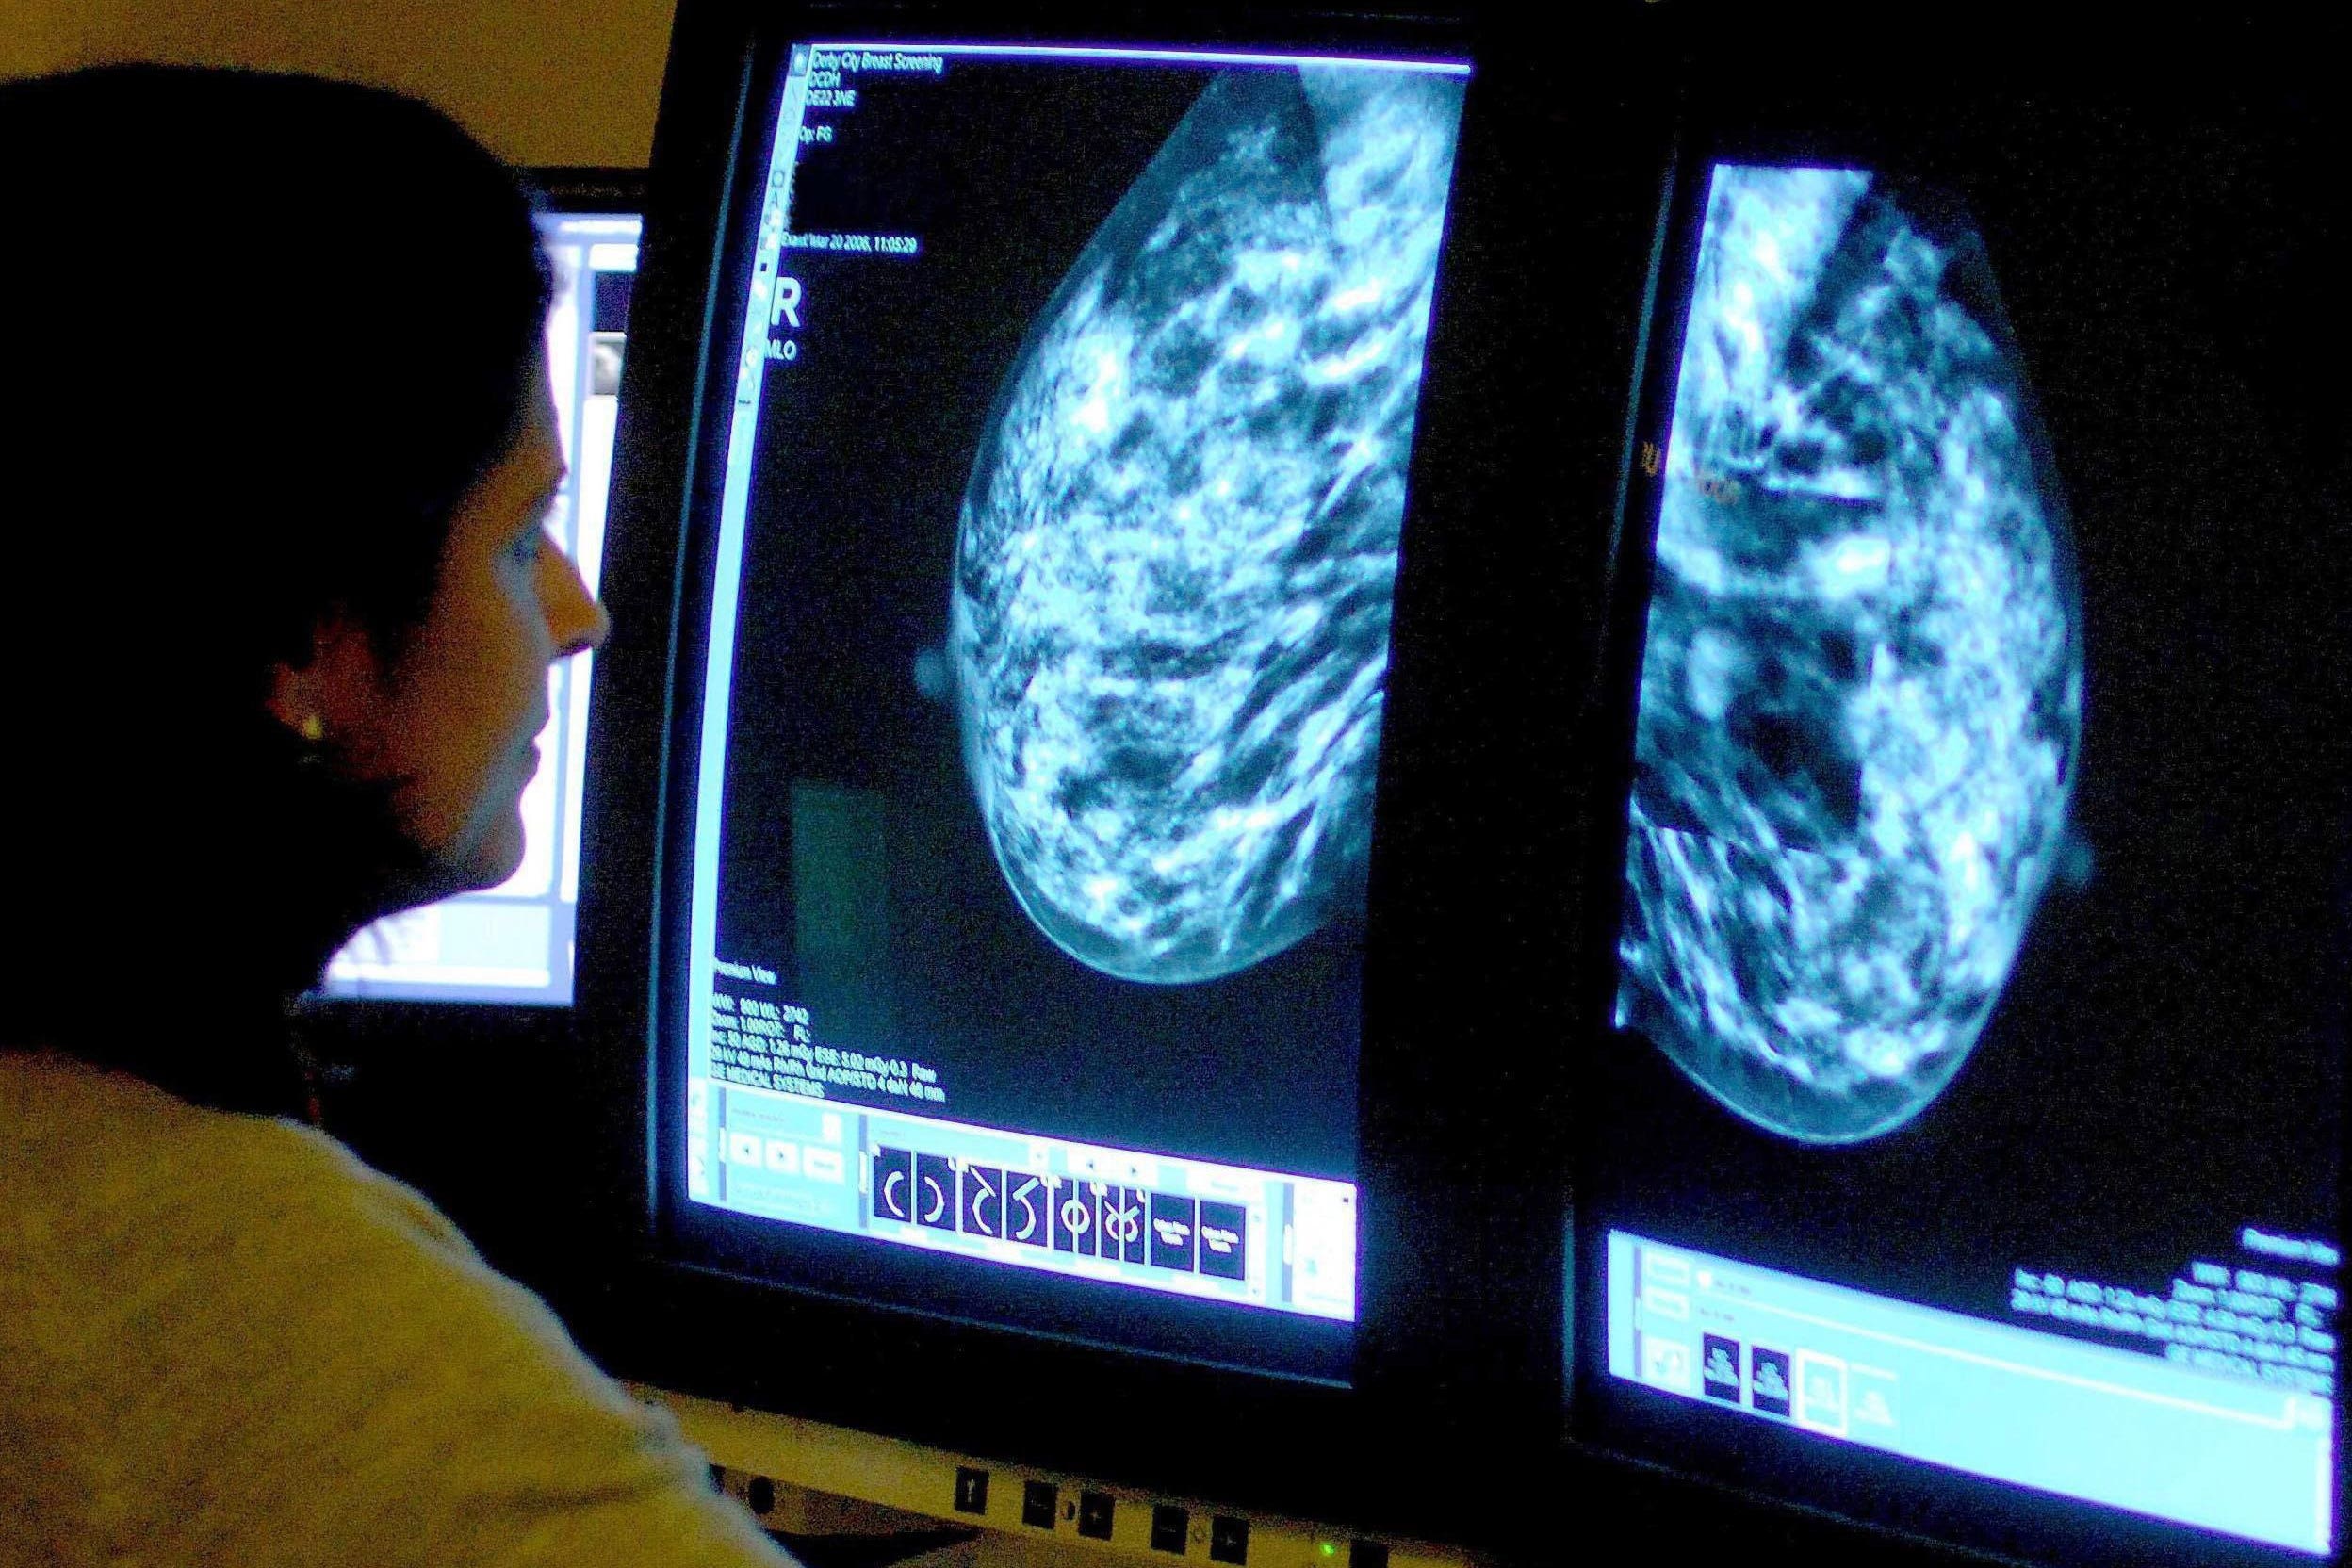

During the appointment, which usually takes about 30 minutes, two X-rays, known as mammograms, will be taken of each breast.